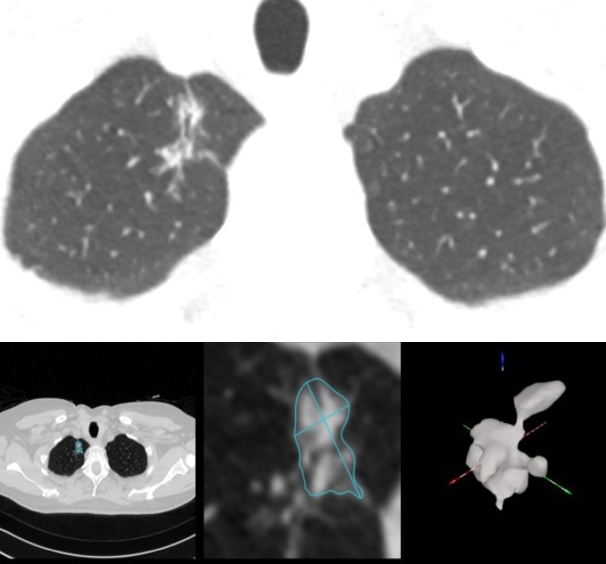

Figure : Adénocarcinome pT1b du lobe supérieur droit détecté par IA.